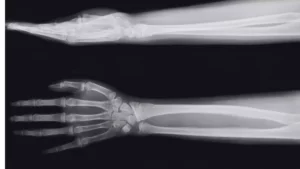

Cirurgia de Antebraço

Fratura do Antebraço

Navegando pela Recuperação da Fratura do Antebraço Bem-vindos ao nosso espaço de aprendizado onde descomplicamos os aspectos médicos para você. Se você ou alguém próximo